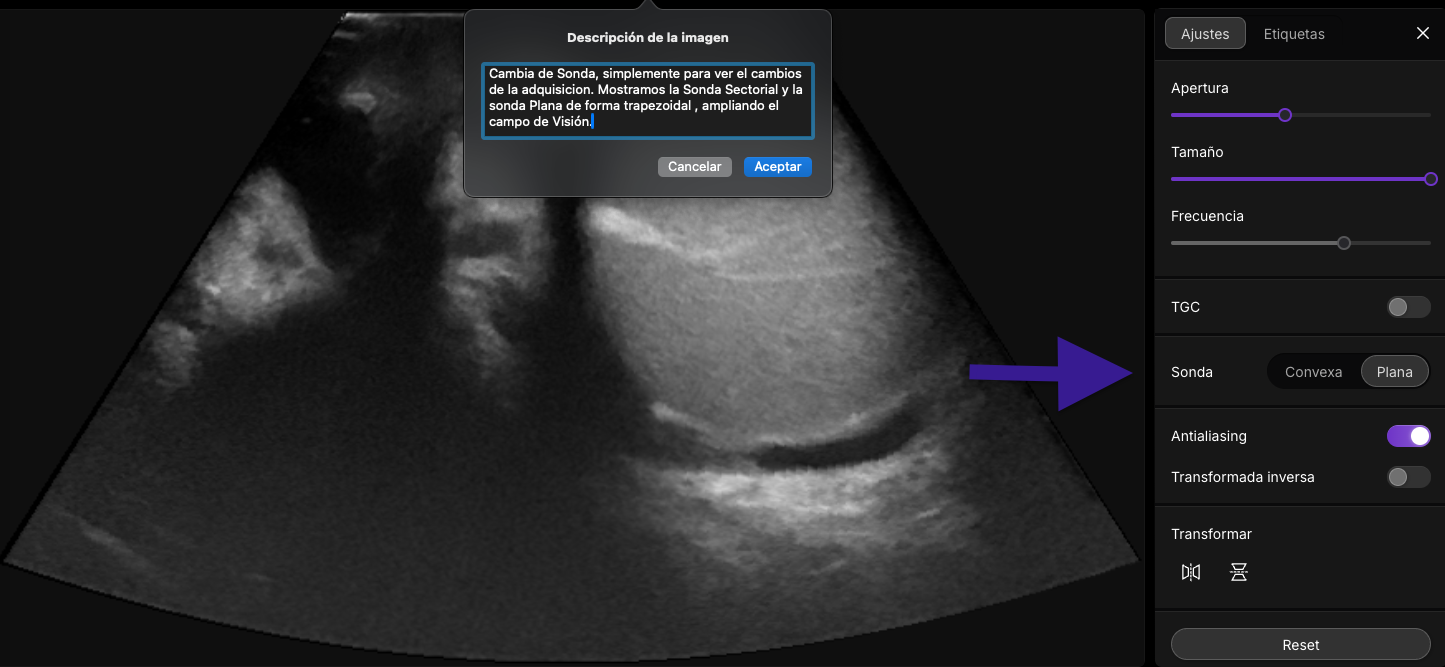

¡Importante! Al pulsar sobre la imagen accederás a un jugable docente.

Interacción Sonido con tejidos: Just do It!

Figura 5: Tipos comunes de transductores de ultrasonido ( si presionas en sobre la imagen podras ver una animacion gráfica de los diferntes tipos transductores )]

👉 Pulsa sobre la imagen para acceder.

Figura 6: Accede a Imagine Ultrasound Y Cambia de Sonda]